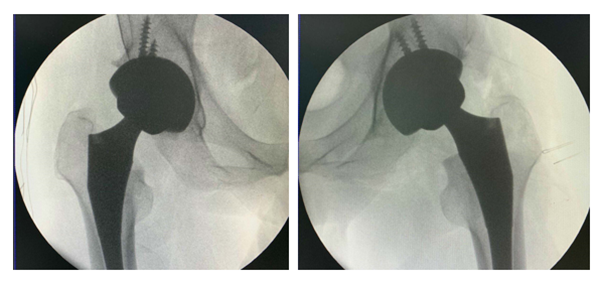

圖五 圖六

針對(duì)周先生的情況,李寬新主任、張衡博士在手術(shù)前進(jìn)行了詳細(xì)完備的術(shù)前設(shè)計(jì)(圖四),并在3Dbody、Mimics、Magic軟件上進(jìn)行入路設(shè)計(jì)和模擬手術(shù)(圖五、六),計(jì)算出髖臼杯和股骨柄大小及髖臼杯外展角、前傾角、旋轉(zhuǎn)中心位置等關(guān)鍵指標(biāo)。6月16日在周建生教授的指導(dǎo)支持下,由李寬新主任、張衡博士在我院成功應(yīng)用微創(chuàng)OCM入路聯(lián)合Harris窩技術(shù)為患者實(shí)施一期雙側(cè)人工全髖關(guān)節(jié)置換術(shù)。手術(shù)切口僅7cm,術(shù)中出血量約80ml。(圖七)

術(shù)中髖關(guān)節(jié)X線示:髖臼假體旋轉(zhuǎn)中心、前傾角、外展角良好,實(shí)現(xiàn)了精準(zhǔn)置換(圖八),患者目前恢復(fù)良好(圖九)。